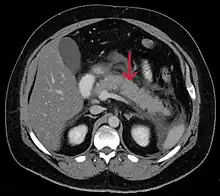

A contrast-enhanced CT scan is usually performed more than 48 hours after the onset of pain to evaluate for pancreatic necrosis and extrapancreatic fluid as well as predict the severity of the disease. CT scanning earlier can be falsely reassuring.